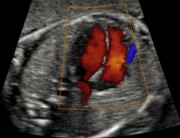

این تصویر در حال ارائه معاینه داپلر (نقشه رنگی) قلب جنین در هفته 22 است. رنگ قرمز جریان خون را از دهان به بطن چپ در طی دیاستول قلب نشان می دهد.